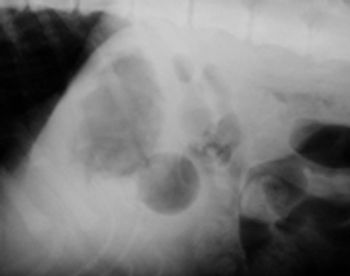

A 9-month-old intact male Labrador retriever was presented two weeks after it swallowed a Ping-Pong ball.